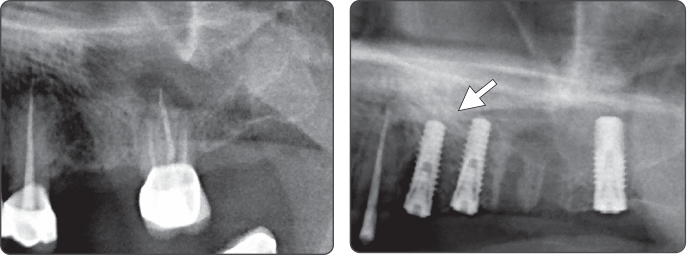

2. Sinus Lift (Ø5.0 Fixture)

▶ Immediate Implantation and Sinus Lift Technique with Tap Drill (Ø5.0 Fixture)

- 提升上颌窦时,建议采用一起使用上颌窦提升钻和扩张钻的手术方式。

- 以Ø3.2扩张器代替点钻使用时,可轻松地进行手术。

- 骨质为D2时,植入Fixture前使用最后钻,注意不要过度施压于周边齿槽骨。